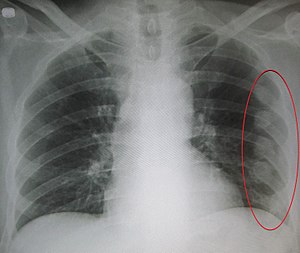

Рентгенологи используют рентген грудной клетки, чтобы искать следующее:

«Три или более смежных ребра сломаны в двух или более местах. Клинически это может быть сегмент, состоящий всего из одного или двух ребер, и он может действовать как сегмент окна»

КТ является более точной методикой при тяжелых тупых травмах.